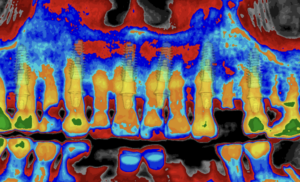

6.2 Inserción del implante

- Colocar el implante a través de la guía si el sistema lo permite, o retirar la guía si la inserción es libre.

- Verificar el torque de inserción y la estabilidad primaria.

6.3 Comprobación final

- Asegurar que el implante tiene la posición tridimensional exacta según el plan digital.

- Colocar los pilares transepiteliales si procede (por ejemplo, AXA).

- Realizar fotografías o escaneado intraoral para documentar el caso y avanzar hacia la fase protésica.